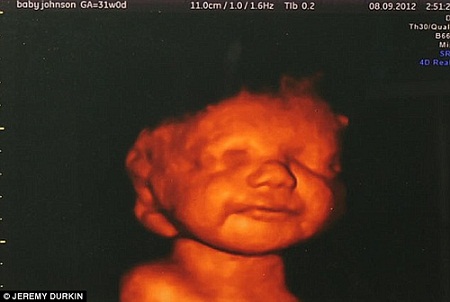

卢西恩的三维扫描图

但当医生为胎儿进行详细的三维扫描时,卡提亚从屏幕中看到胎儿不时“微笑”,还在其腹中摆动手脚,展现了极强的生命力。她认为,胎儿的残障不阻碍他享受生命,因此决定不论儿子出生后命运如何,都不会剥夺他生存的权利。